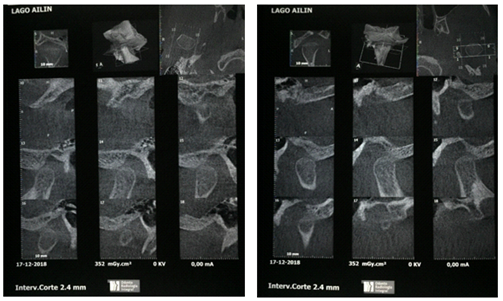

At IUCEDDU, in addition to the final cephalometrics corresponding to each case, we are starting to perform CONE BEAM CT scans of the TMJs to evaluate the effects of the twin blocks. These examinations are performed by means of single cone beam x-ray acquisition with the patient's mouth slightly open and subsequent axial slices of 0.2mm thickness. So far, no pathological changes have been observed in the condyles or glenoid cavities of patients treated with twin blocks; on the contrary, adaptive changes such as flattening of the condyles have been observed. All treated patients are symptom-free several years after the end of the treatment.

Following are images of the right and left TMJs of Dr. Marcelo Mochó's patient A.A. as an example of the studies performed at the Institute, where no particularities were observed in the TMJs (Figure 13). Also shown is the control tomography of patient M.R. after 5 years of treatment. The condyles are slightly flattened (Figure 14).